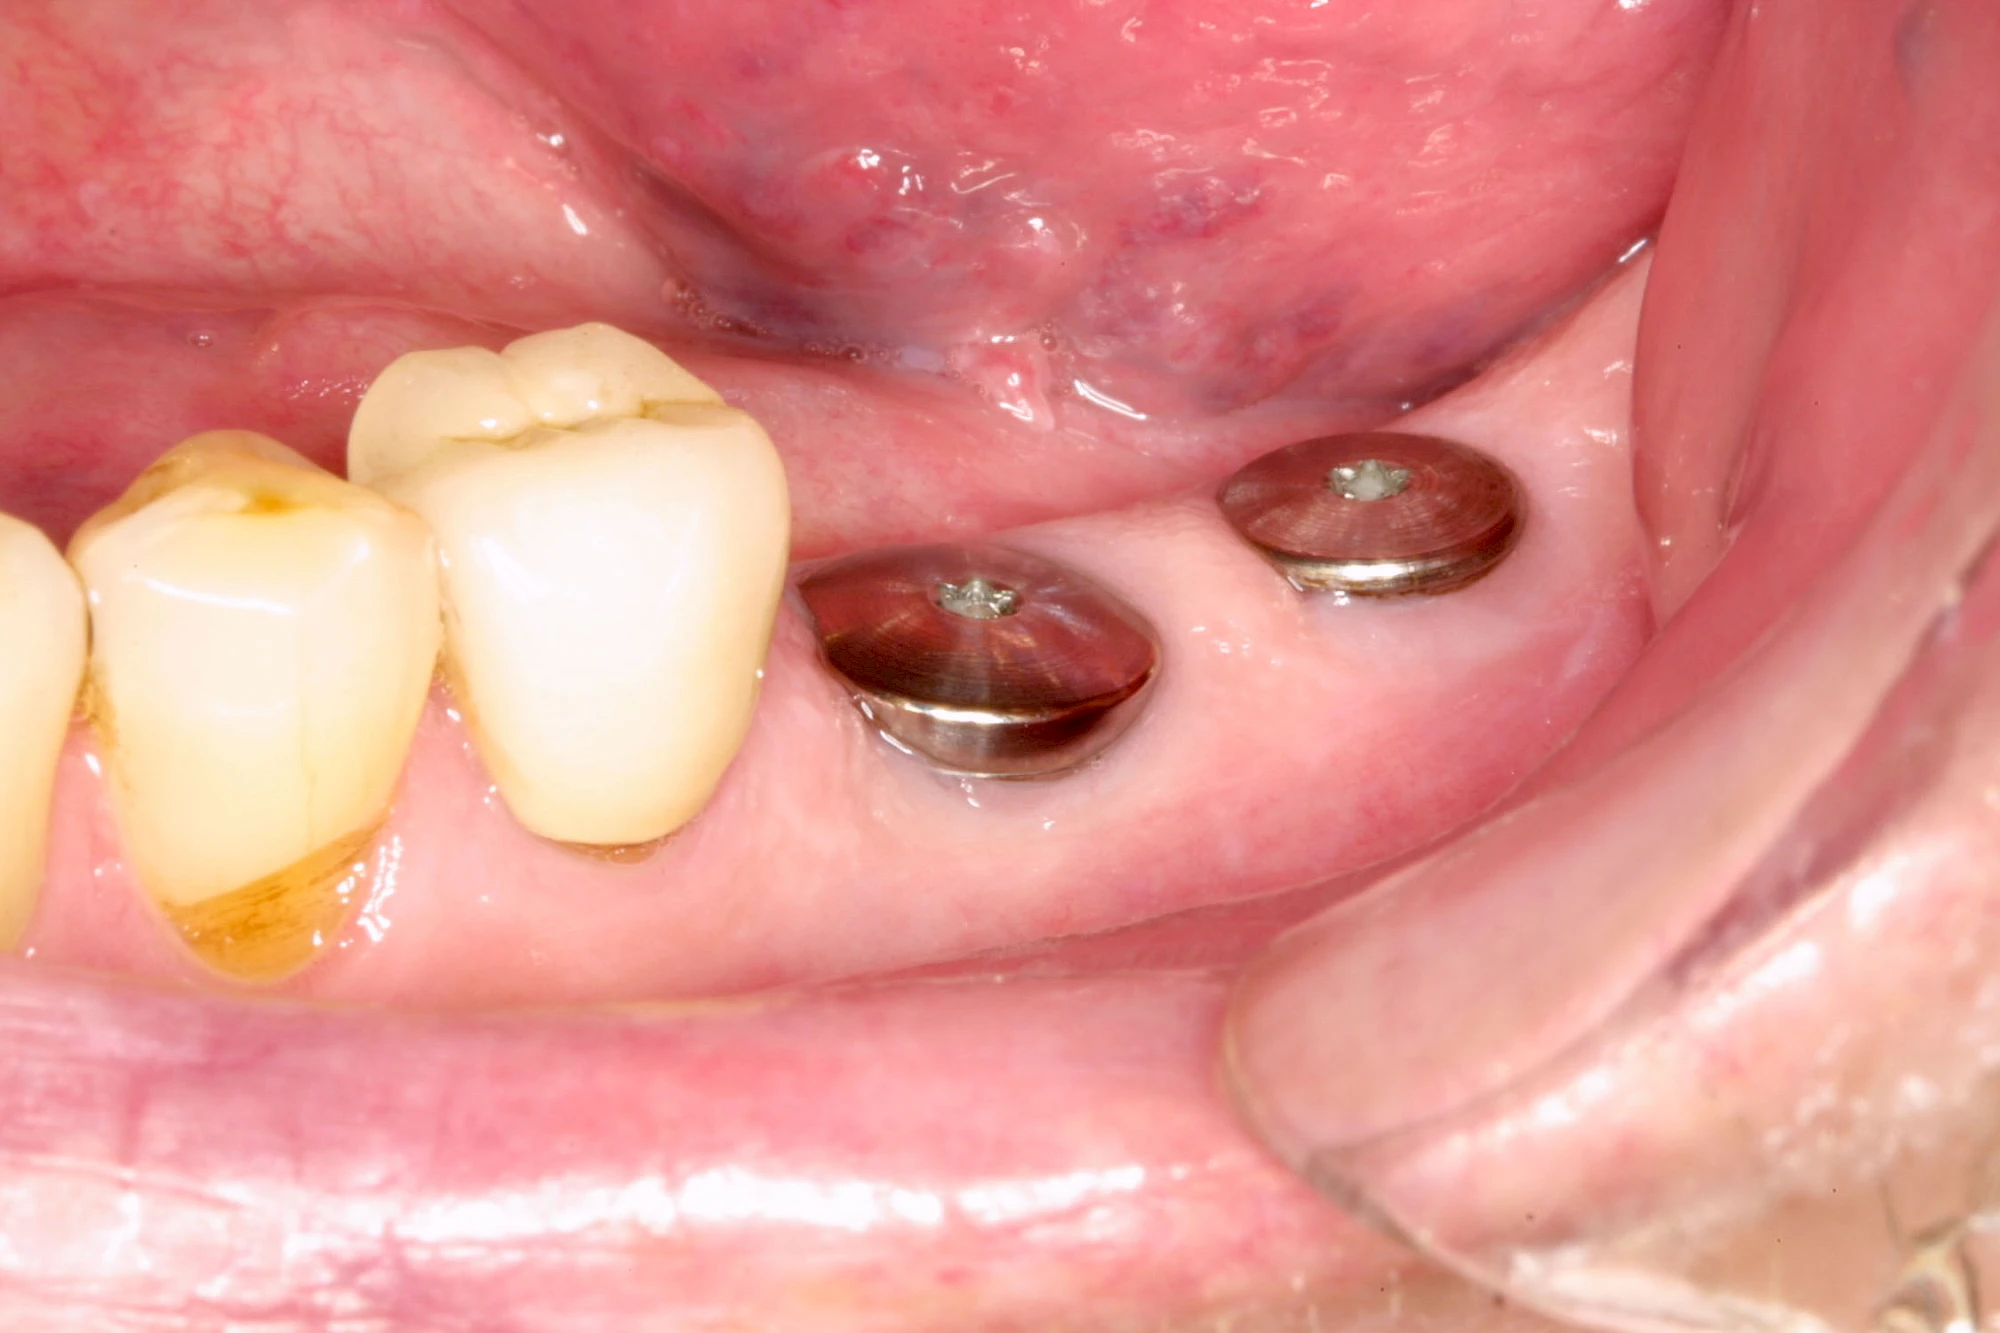

Implantate: Bestandteile

Implantate sind künstliche Zahnwurzeln. Nach einer gewissen Einheilzeit im Knochen (meist 3-6 Monate) erfolgt über einen separaten Aufbau (Abutment) die Befestigung einer Krone bzw. Brücke oder Zahnprothese.

In seltenen Fällen sind Implantate samt Aufbau aus einem Stück gefertigt. Auch gibt es Situationen, die ein Früh- oder sogar eine Sofortbelastung erlauben – dann kann die Einheilzeit der Implantate in den Knochen verkürzt oder sogar gänzlich darauf verzichtet werden.